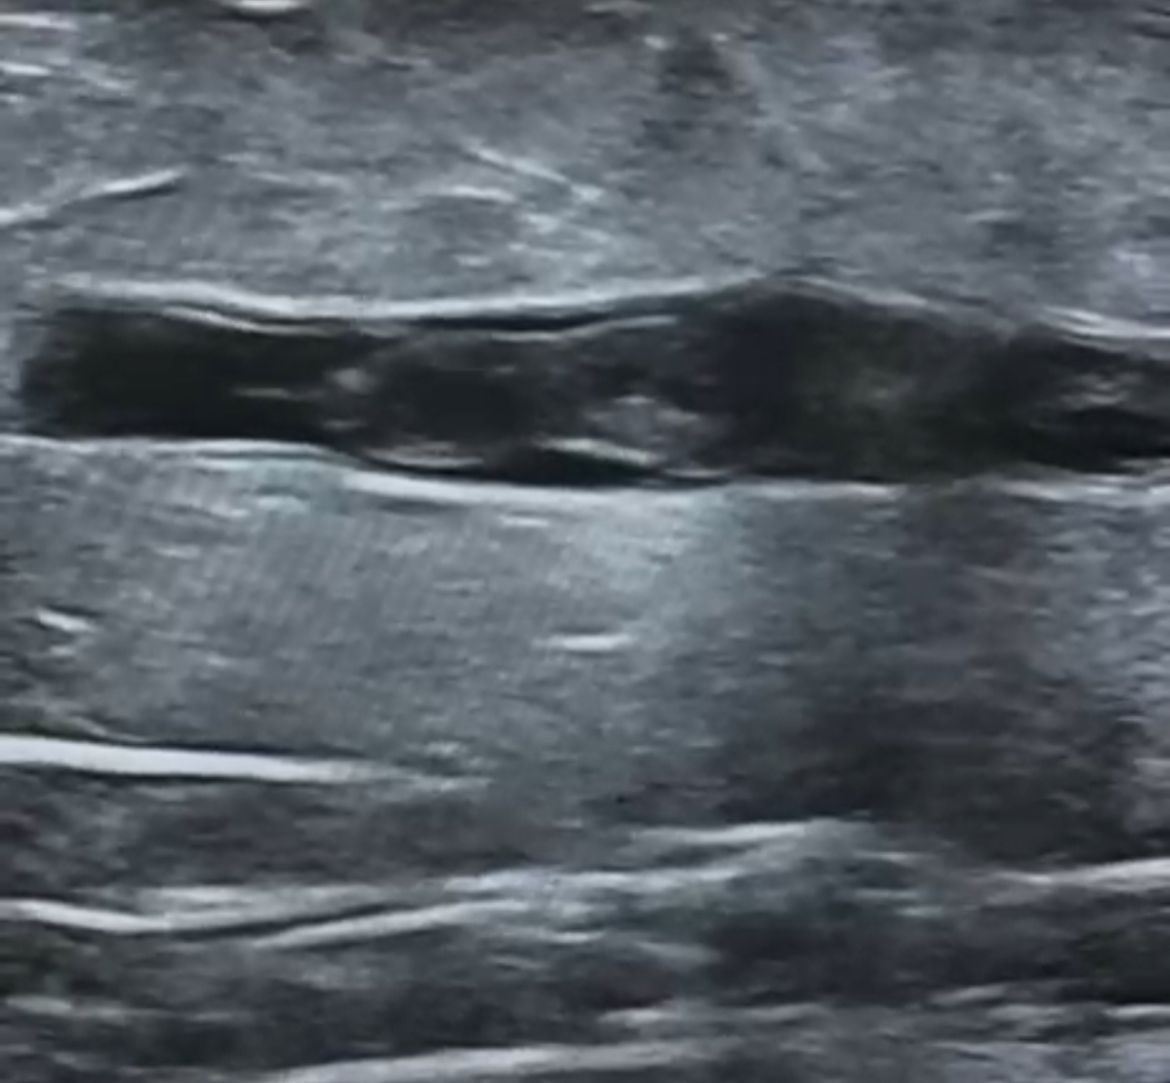

Врач УЗИ Жанар Нурмаханбетова провела пациенту ультразвуковое доплеровское исследование сосудов нижних конечностей. В результате было выявлено наличие опасного флотирующего тромба в большом подкожном венозном стволе на участке между бедром и голенью справа.

По словам специалистов, флотирующий тромб — крайне опасное состояние, так как тромб не полностью прикреплён к стенке сосуда. Если такой тромб с током крови поднимется выше, он может закупорить лёгочную артерию и привести к летальному исходу.